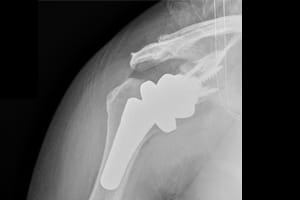

AFTER:

This is an x-ray after surgery demonstrating a reverse total shoulder replacement.